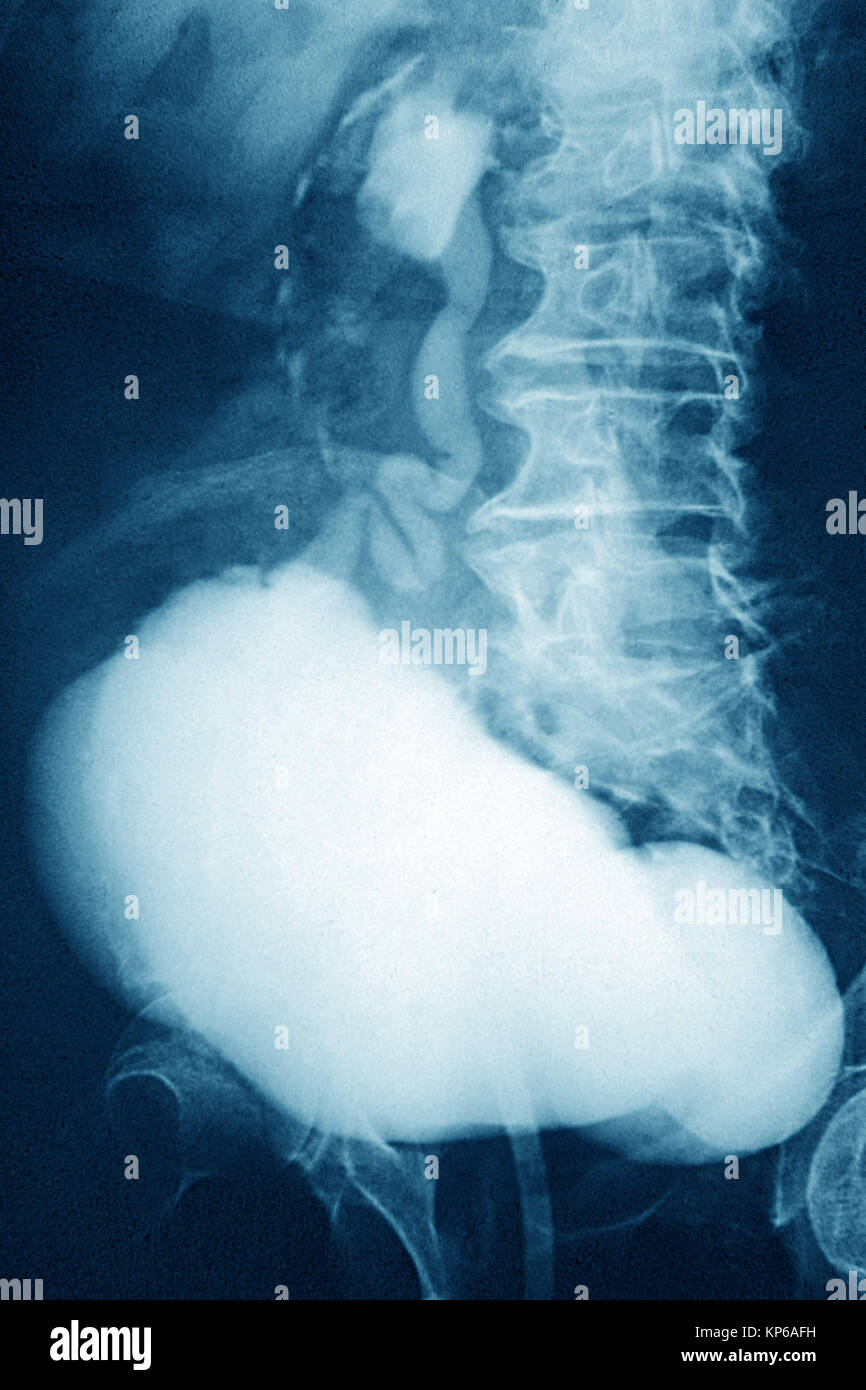

From www.alamy.com

DIVERTICULUM IN BLADDER, XRAY Stock Photo Alamy What Is A Diverticulum In The Bladder Bladder diverticula are protrusions of the bladder urothelium and mucosa via muscle fibers of the bladder. Diverticula) is an outpouching from the bladder wall, whereby mucosa herniates through the bladder wall. The bladder diverticulum is an outpouching of the bladder wall (powell et al., 2009). A bladder diverticulum is a pouch or sac that forms in the bladder wall, causing. What Is A Diverticulum In The Bladder.

DIVERTICULUM IN BLADDER, XRAY Stock Photo Alamy What Is A Diverticulum In The Bladder The bladder diverticulum is an outpouching of the bladder wall (powell et al., 2009). Bladder diverticula are protrusions of the bladder urothelium and mucosa via muscle fibers of the bladder. It may be solitary or. Bladder diverticula are outward bulges of the inner (epithelial) lining of the urinary bladder through a defect in its muscle layer. A bladder diverticulum is. What Is A Diverticulum In The Bladder.